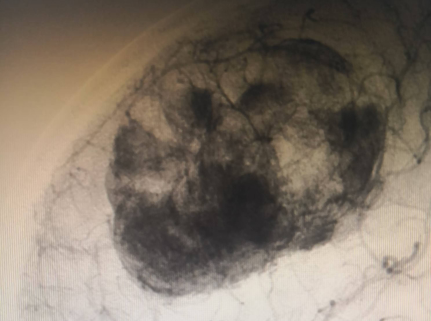

神经外科血管介入组曲友直副教授、崔刚副教授和高攀主治医师对肿瘤进行了瘤栓塞治疗,有效减少了肿瘤的血供,为后续的手术切除降低了风险。栓塞治疗后,神经外科王睿智副主任、高李贵副教授和董全主治医师在麻醉科、心内科、输血科等科室的全力配合下,凭借精湛的医术和丰富的临床经验,成功为患者切除了病变。手术过程中,麻醉科吕建瑞主任团队全程监控患者的生命体征,确保麻醉安全;心内科团队随时准备应对可能出现的心脏问题;输血科团队则确保充足的血液供应,以备不时之需。多学科的通力合作,为手术的成功提供了坚实的保障。